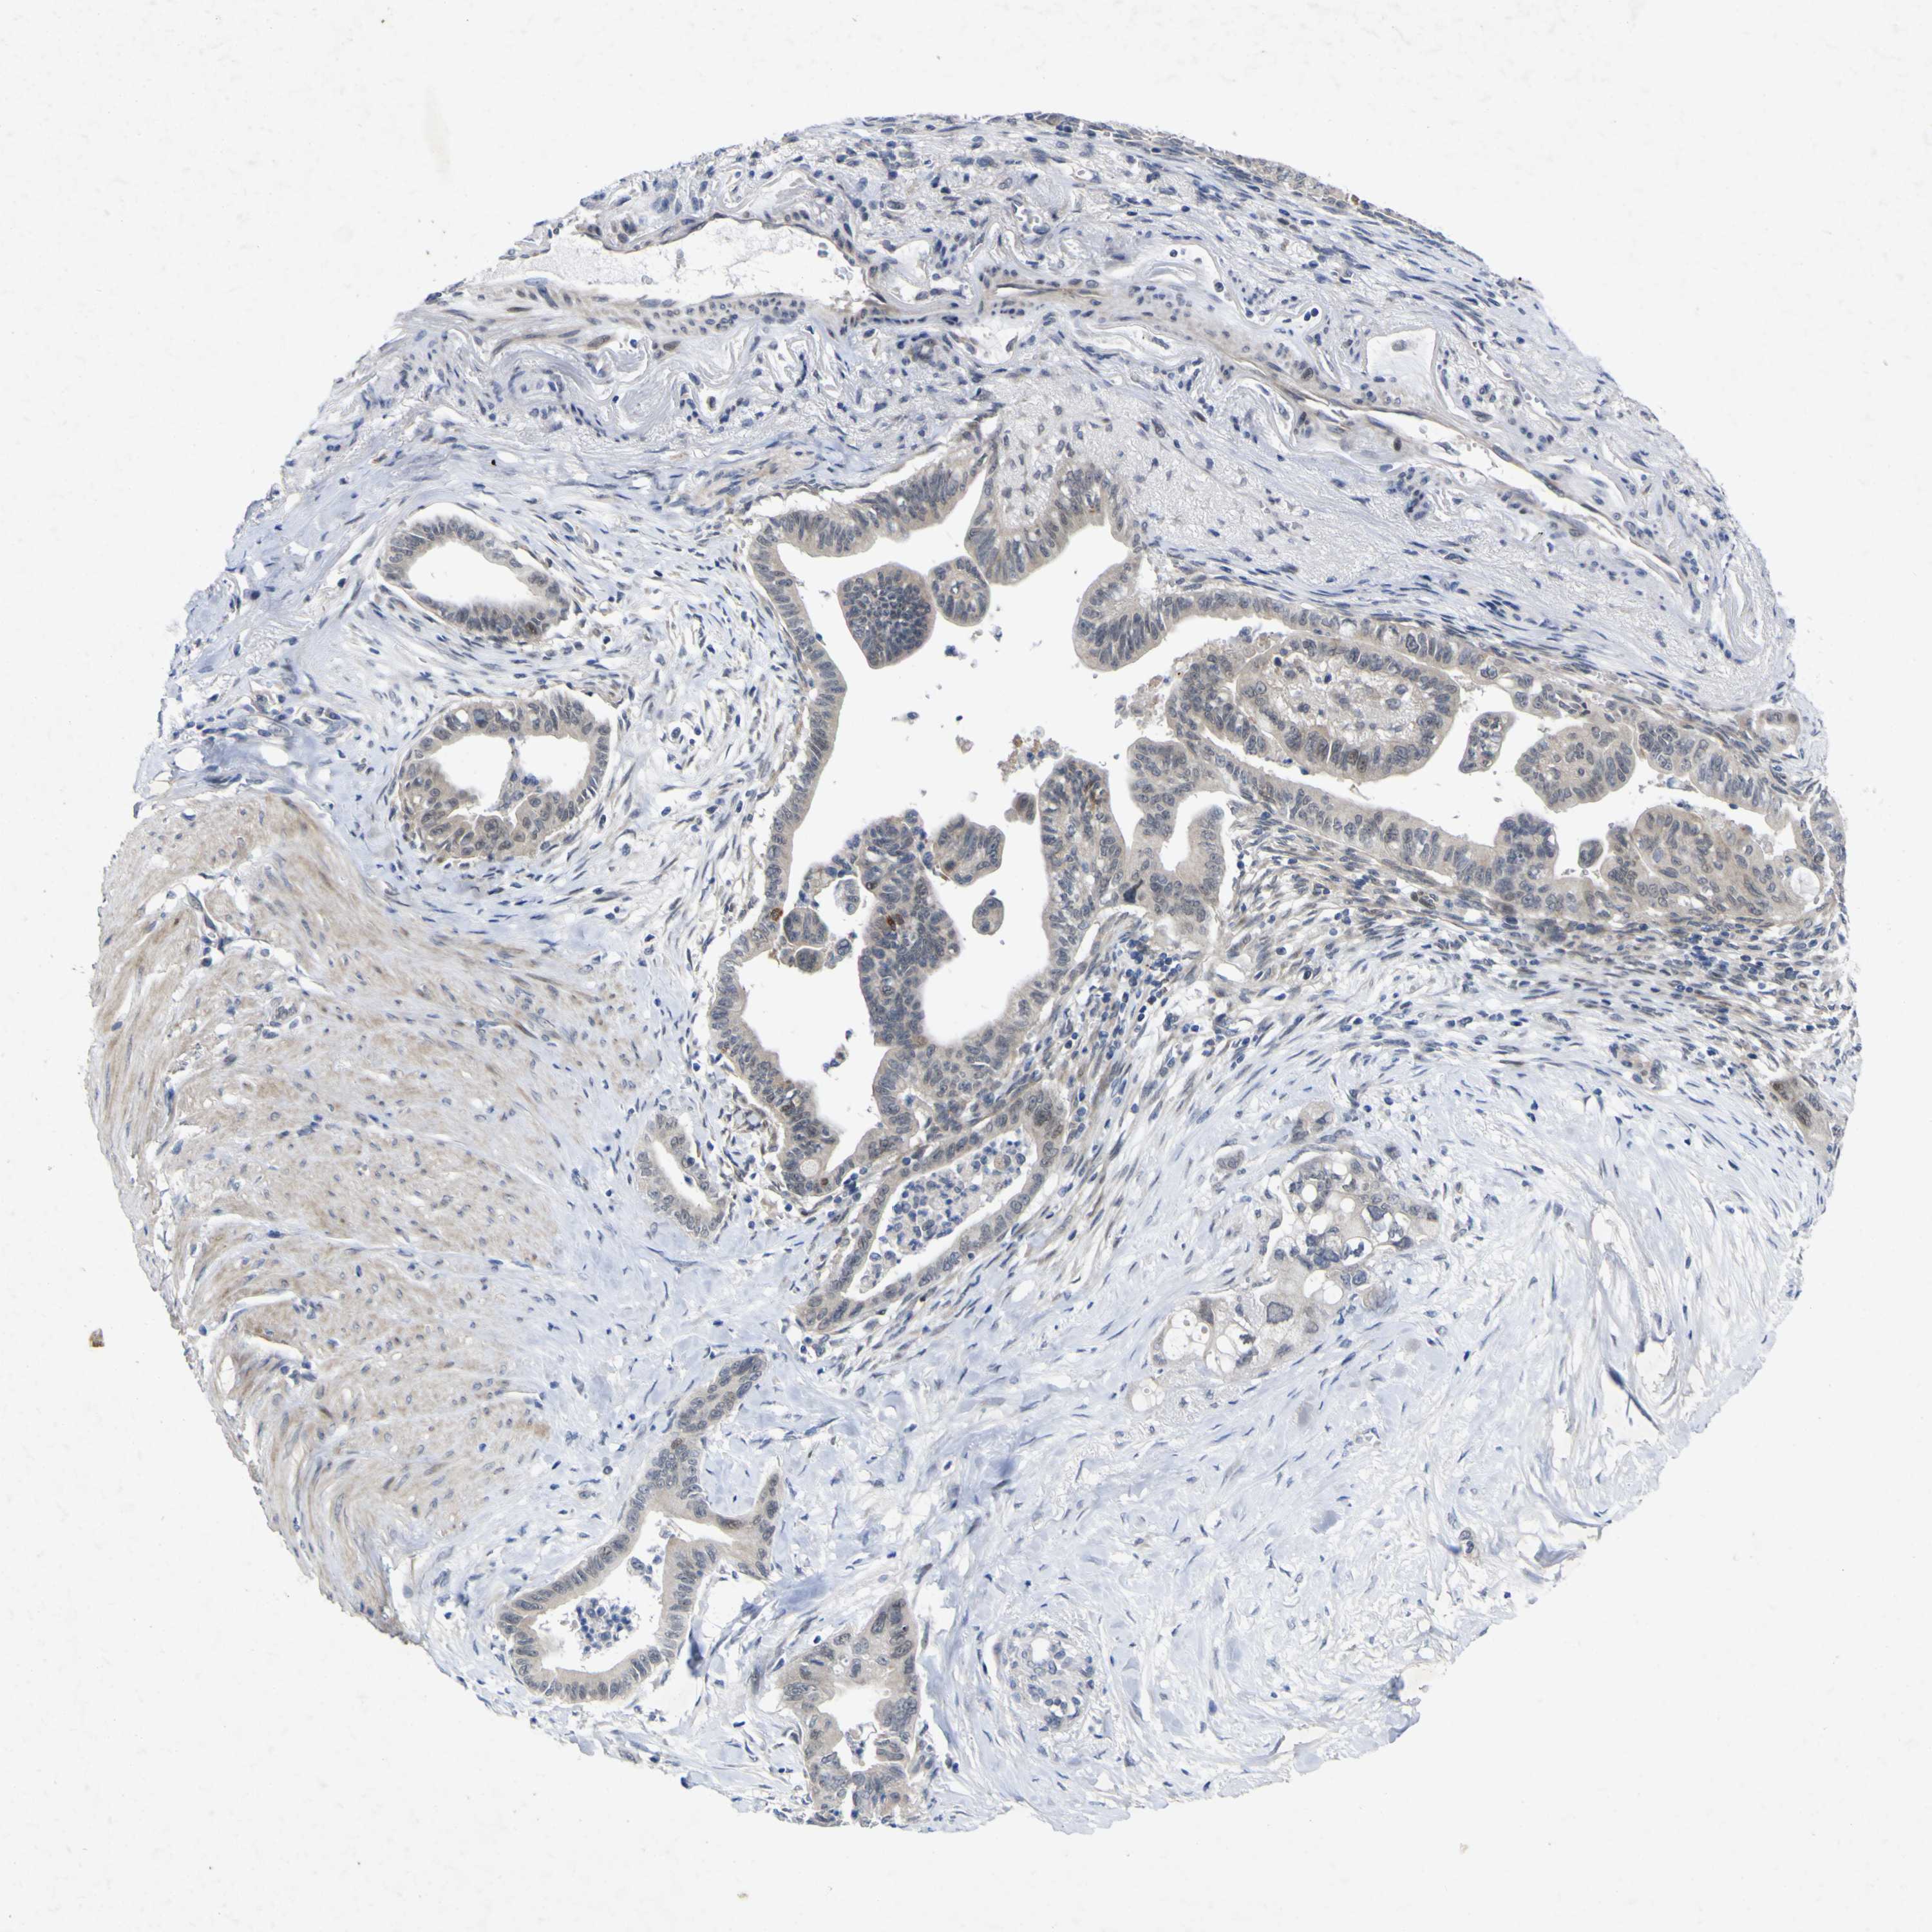

PANCREATIC CANCER - Protein expressioni

A mouse-over function shows sample information and annotation data. Click on an image to view it in a full screen mode. Samples can be filtered based on level of antibody staining by selecting one or several of the following categories: high, medium, low and not detected. The assay and annotation is described here.

Note that samples used for immunohistochemistry by the Human Protein Atlas do not correspond to samples in the TCGA dataset.

Antibody stainingi

Antibody staining in the annotated cell types in the current human tissue is reported as not detected, low, medium, or high, based on conventional immunohistochemistry profiling in selected tissues. This score is based on the combination of the staining intensity and fraction of stained cells.

Each image is clickable and will lead to virtual microscopy that enables deeper exploration of all samples and also displays staining intensity scores, fraction scores and subcellular localization as well as patient and tissue information for each sample.

Antibody HPA018127

Antibody HPA027887

Antibody CAB012302

Adenocarcinoma, NOS

Adenocarcinoma, metastatic, NOS